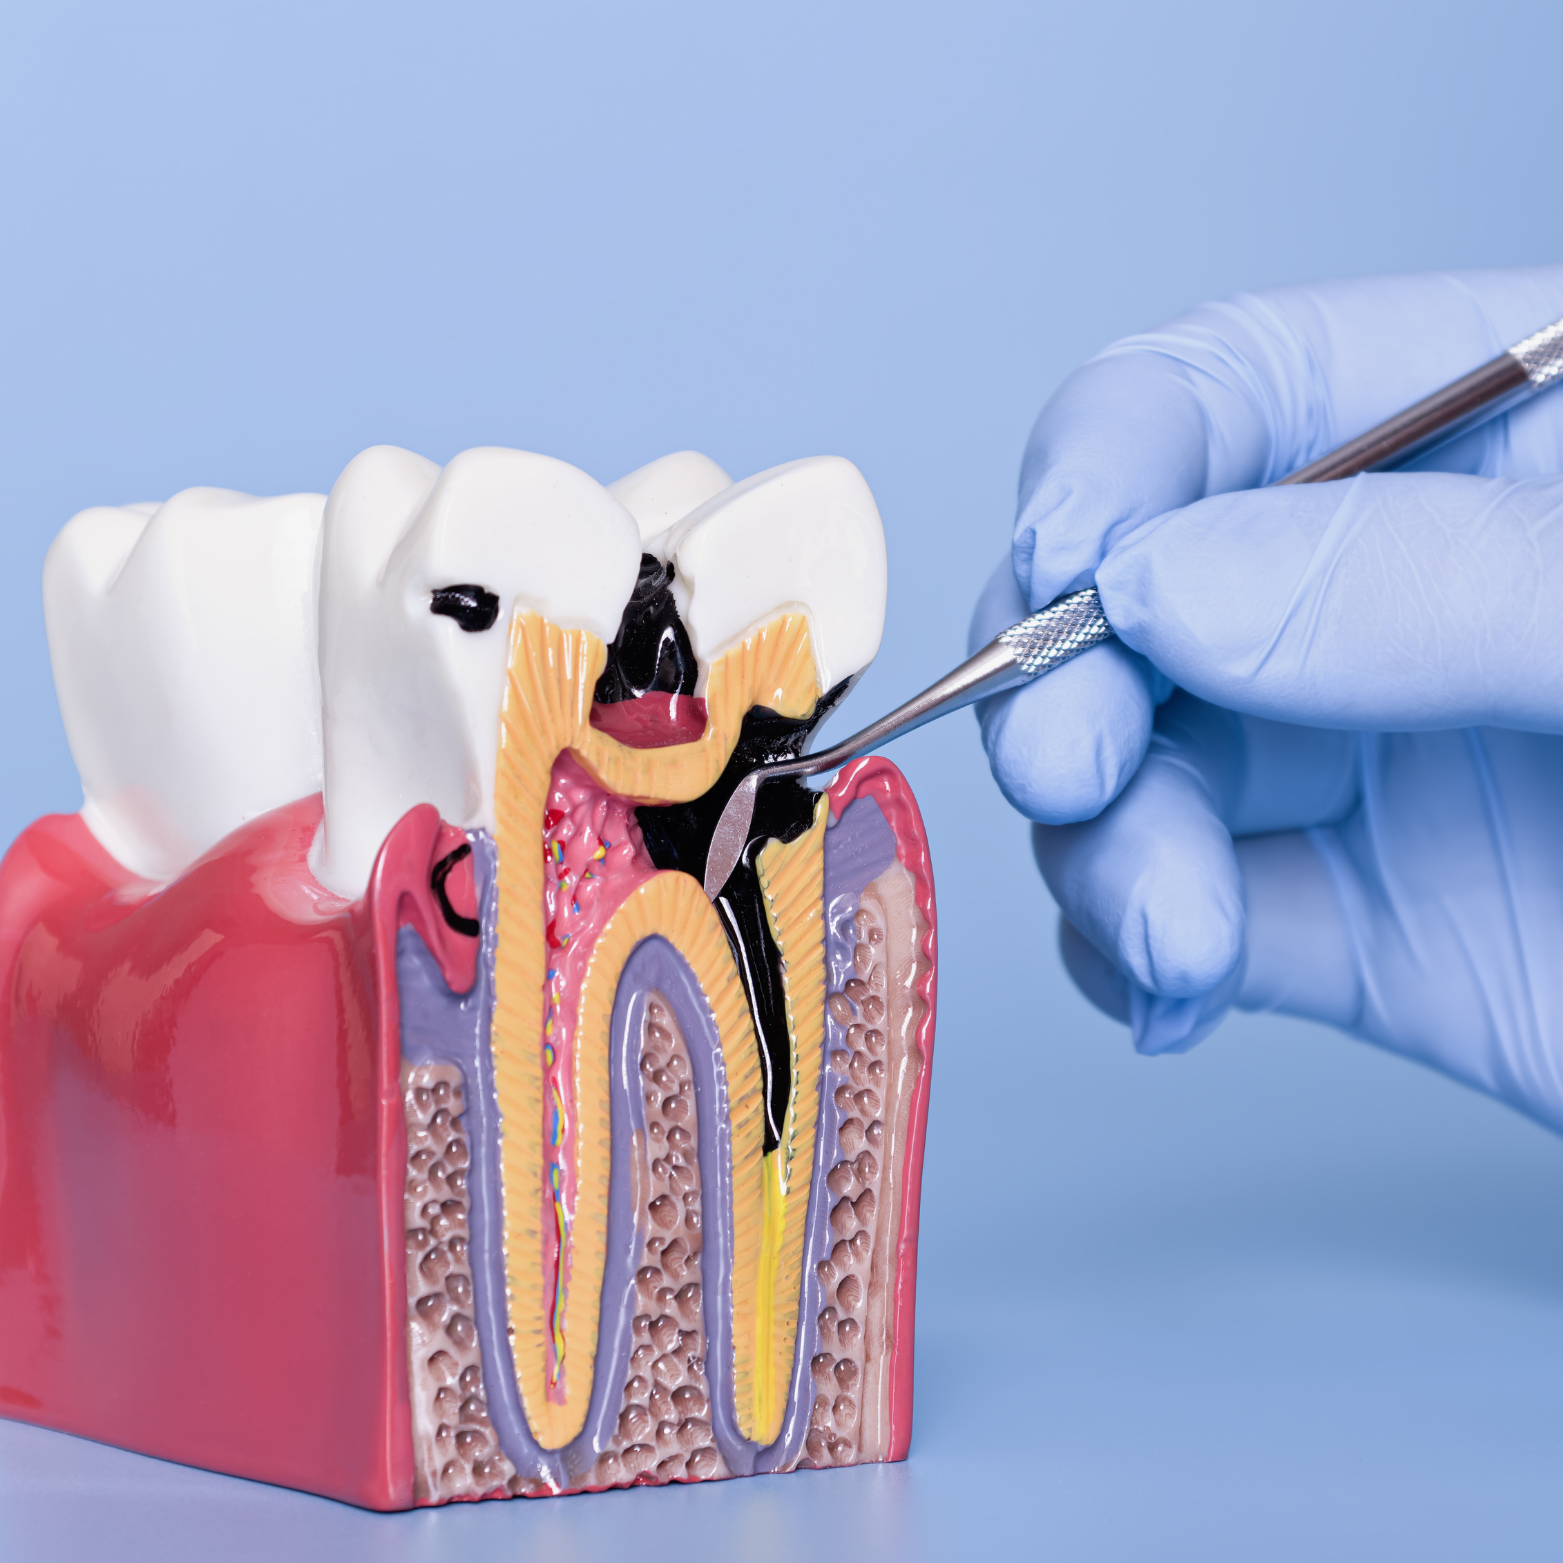

ROOT CANAL TREATMENT

We focuses on removing infection and preserving your natural tooth while putting your comfort first throughout the procedure; our team uses gentle anesthesia techniques, calming communication, and pain-management protocols to minimize anxiety and discomfort.

We also employ advanced technology—digital imaging, electronic apex locators, and rotary instruments—to precisely locate and clean the root canals, ensuring thorough disinfection and accurate shaping for a reliable long-term outcome.